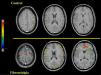

Recientemente, en apoyo al modelo etiológico de una alteración del sistema nervioso central se ha observado en estos pacientes un patrón anormal de la activación funcional cerebral (estudiada mediante RMf)13,14,15,16 como respuesta cerebral a varias intensidades de estímulos mecánicos o térmicos dolorosos y no dolorosos13,14,15. Los estudios de RMf caracterizan a este patrón de respuesta cerebral por un incremento de la sensibilidad y un aumento de la respuesta cerebral al dolor a estímulos nociceptivos de baja intensidad pero subjetivamente percibidos como moderadamente dolorosos por el paciente con FM en términos de extensión y de magnitud de la activación y en las regiones cerebrales que configuran la “matriz neural” del dolor13. Deus et al (2006) plantearon un estudio de RMf en pacientes con diagnóstico clínico de FM con un enfoque eminentemente clínico. En éste, se administró a los pacientes una presión mecánica de 4kg/cm2 durante la adquisición de la RMf, de forma similar a la intensidad recomendada para ejercer la palpación digital sobre los puntos sensibles durante la exploración de los pacientes con FM. Los resultados permitieron constatar que una proporción significativa de pacientes diagnosticados de FM, con un bajo umbral doloroso, presentaban una consistente activación de la “matriz neural” del dolor a estímulos mecánicos de baja intensidad16 (figura 2). Estos resultados muestran una susceptibilidad central para la respuesta al dolor22 y la posibilidad de utilizar la RMf como método diagnóstico complementario al método convencional16.

Figura 2. Cortes axiales de resonancia magnética funcional. En la porción superior de la figura se muestran los resultados de la activación funcional cerebral de un voluntario sano en respuesta a 4kg de peso. Se pueden observar cambios significativos únicamente en el área sensitivo-motora contralateral al dedo pulgar estimulado. En la porción inferior de la figura se muestran los resultados de la activación funcional cerebral de un paciente con diagnóstico clínico de fibromialgia. Se observa un patrón de activación de las regiones cerebrales involucradas, normalmente, en la respuesta al dolor. Los cambios fueron significativos en distintas áreas del lóbulo parietal (corteza somatosensorial primaria y corteza somatosensorial secundaria) y del lóbulo frontal, en la ínsula, en los opérculos y en la región de la corteza cingulada anterior. La letra t expresa el test de la t de Student.

De acuerdo con este último supuesto teórico descrito, en un reciente estudio pendiente de publicación y que presentó en comunicación oral el grupo de investigación al que pertenece el autor de este artículo, se ha delimitado la “matriz neural” implicada en la respuesta a un estímulo mecánico equivalente a 4kg/cm2 de peso, que no causa dolor relevante en un grupo control de voluntarios sanos, y de acuerdo con el curso temporal real de la respuesta cerebral y no al curso temporal que define la aplicación de un estímulo nociceptivo. En primer lugar, esta matriz implica una mayor perfusión sanguínea cerebral de la SI contralateral a la extremidad estimulada y de la SII. Esta región se activa tanto en los pacientes con FM como en los pacientes del grupo control de voluntarios sanos con una duración equivalente, en ambos grupos, a la duración del estímulo nociceptivo aplicado. Ambas regiones corticales se consideran como áreas cerebrales involucradas en la dimensión sensorial del procesamiento del dolor1,29. En segundo lugar, se constata una importante y significativa activación funcional, con una duración temporal de activación superior a la del estímulo nociceptivo aplicado, de la porción anterior de la ínsula únicamente en el grupo de pacientes con FM. Además, se constata que la activación de esta región, como consecuencia de la aplicación del estímulo doloroso, se encuentra específica y positivamente relacionada con el dolor que experimentan los pacientes con FM (figura 2). Estos resultados están en concordancia con estudios previos que demuestran un importante papel de la región opérculo-insular en el componente afectivo-motivacional de la experiencia dolorosa, al relacionarse con la dimensión emocional del dolor13,14,15,29 y con el grado de angustia que muestra el paciente ante un estímulo doloroso29.